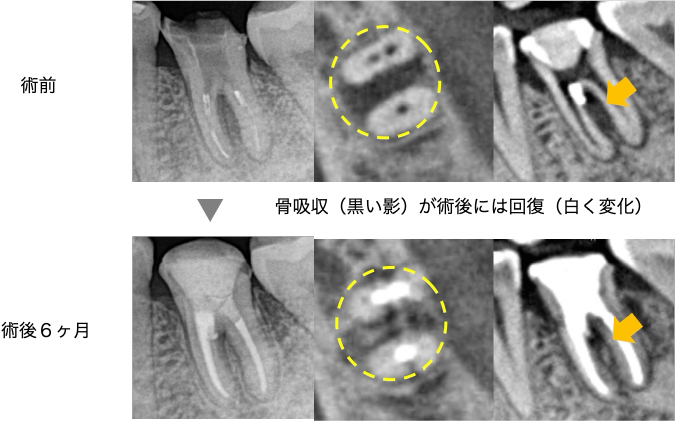

術後6ヶ月のフォローアップ時のレントゲンとCTにて、元々顕著であった骨吸収の回復が認められました。歯周ポケットも10mmだった部位は3mmに減少し、治癒傾向を示しています。